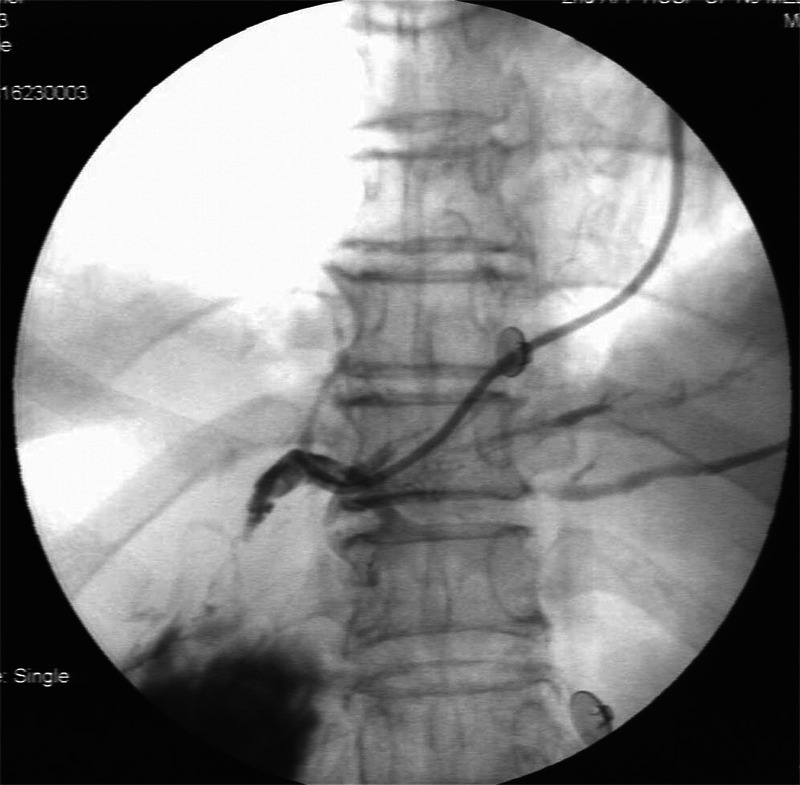

Guidewire technique and nasobiliary duct-assisted secondary EUS-guided biliary drainage.

导丝技术和鼻胆管辅助二次 EUS 引导胆道引流。